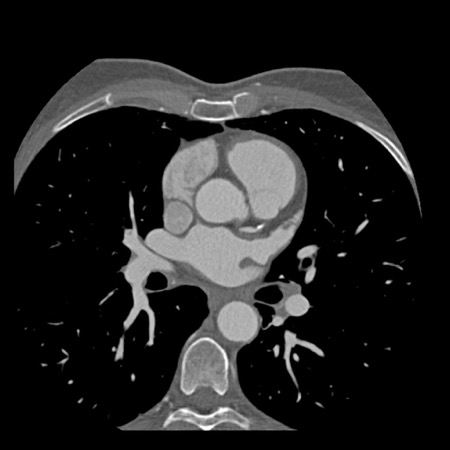

case 1 – CAD-RADS 2/P1

First, scroll through the scan.

Not all images are included. Some images without any abnormalities are skipped

from the series.

How would you describe the findings on the coronary CTA?

The findings are:

- Agatston score of

this patient was 14 (P1). Please, also note the calcification of the aortic valve. - Some partially

calcified and calcified plaques are present in the LAD with mild stenosis

(25-49%). - Calcified-plaque in

the LCX causing minimal stenosis (<25%). - Non-calcified

plaque in the distal RCA causing minimal stenosis (<25%). - This patient classifies

as CAD-RADS 2/P1, which means no further workup is needed.